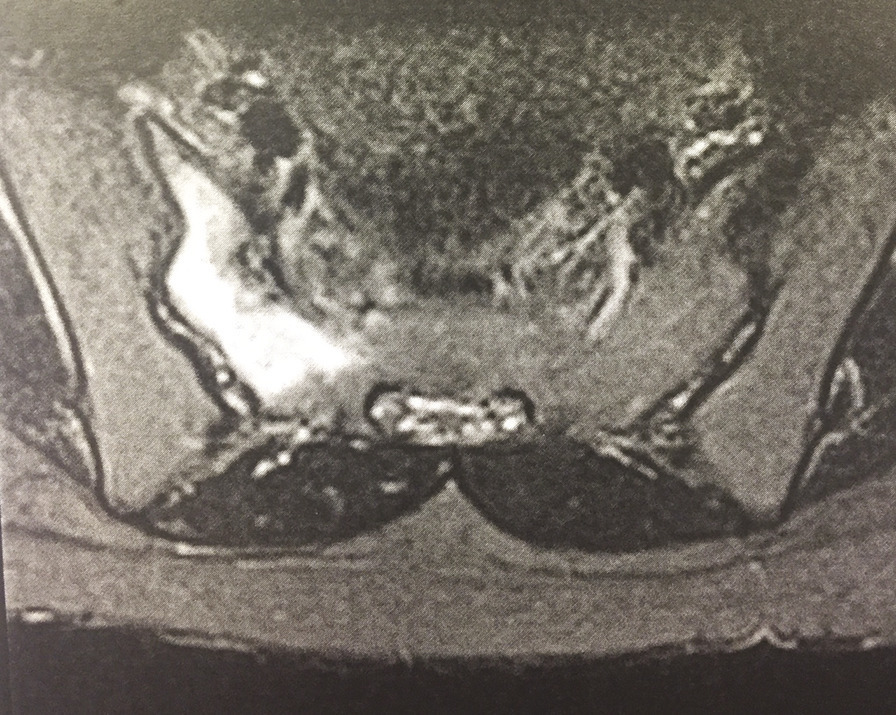

Engagée depuis 2 mois, cette jeune militaire consultait pour des paresthésies des orteils, sans notion de traumatisme aigu. Sédentaire auparavant, elle n’avait aucun antécédent particulier. Son indice de masse corporelle était de 20 kg/m2. L’examen notait une douleur neurogène avec trouble des sensibilités prédominant à l’extrémité du pied droit, sans syndrome radiculaire ni rachidien, d’horaire non mécanique. Le test de Faber était positif. Réalisée en seconde intention, l’IRM du bassin (v. figures) montrait une fracture de contrainte de l’aileron sacré droit. Le bilan biologique était sans particularité. Une cure courte d’anti-inflammatoires non stéroïdiens et la limitation au minimum des activités physiques entraînaient la guérison en 8 semaines.